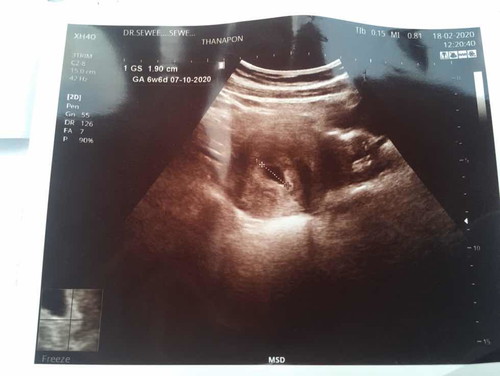

วันนี้เราอัลตราซาวด์มาคุณหมอบอกได้แค่6w ประจำเดือนมาครั้งสุดท้ายวันที่20/12/62 แต่ในแอฟบอก8w ไปซาวด์มาวันนี้เจอแต่ถุงยังไม่เจอตัวเด็ก จะเจอตัวเด็กตอนกี่wค่ะ ขอดูรูปอัลตราซาวด์ของคุณแม่ตอน 6 w หน่อยค่ะ

6วีคยังไม่เจอตัวเด็กจ้าเจอแต่ถุงตั้งครรภ์น้องยังเล็กมากตอนนี้ได้11วีคแล้วเจอตัวน้องค่ะเห็นหัวใจด้วย